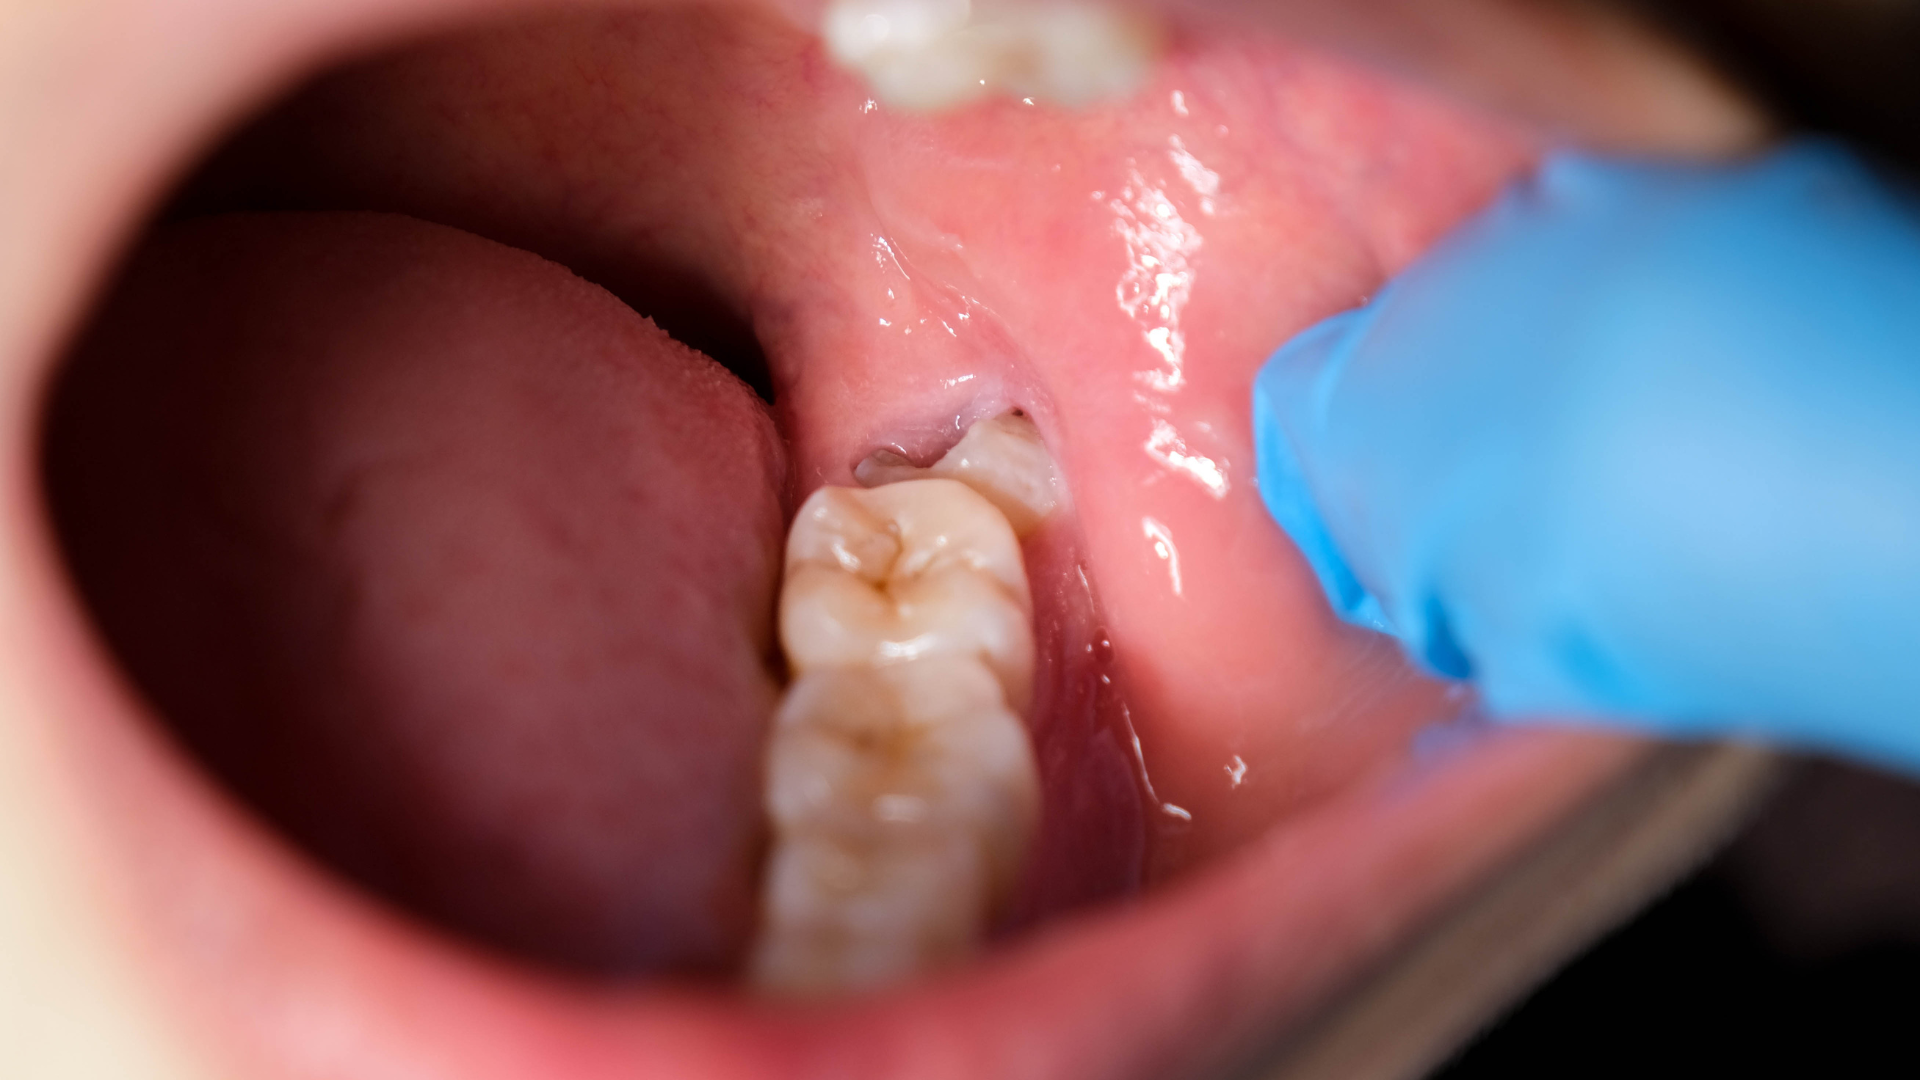

Đánh giá răng mọc ngầm, răng khôn

CT ConeBeam giúp xác định vị trí răng ngầm, đánh giá hướng mọc, mối liên quan với răng kế cận và dây thần kinh, thông tin đặc biệt quan trọng trước khi nhổ răng khôn phức tạp.

- Nhổ răng khôn khó, răng ngầm;